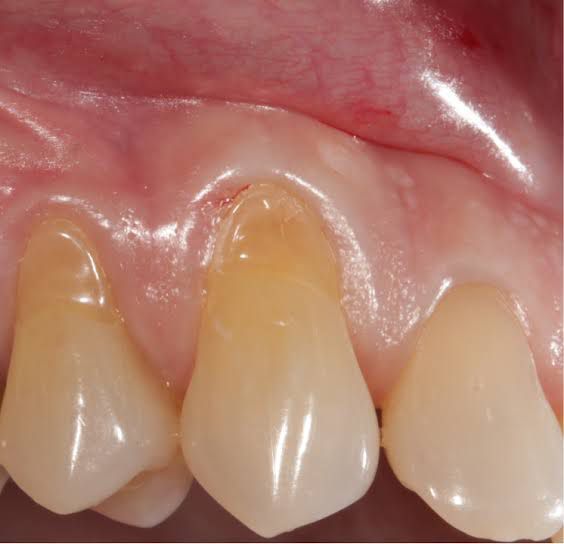

What Is Dental Abrasion? Dental abrasion is another form of dental damage caused by the forces applied to the teeth. Rather than being caused by tooth on tooth contact, abrasion is typically caused by outside elements, like aggressively brushing the teeth. Abrasion begins with the wearing down of the enamel.